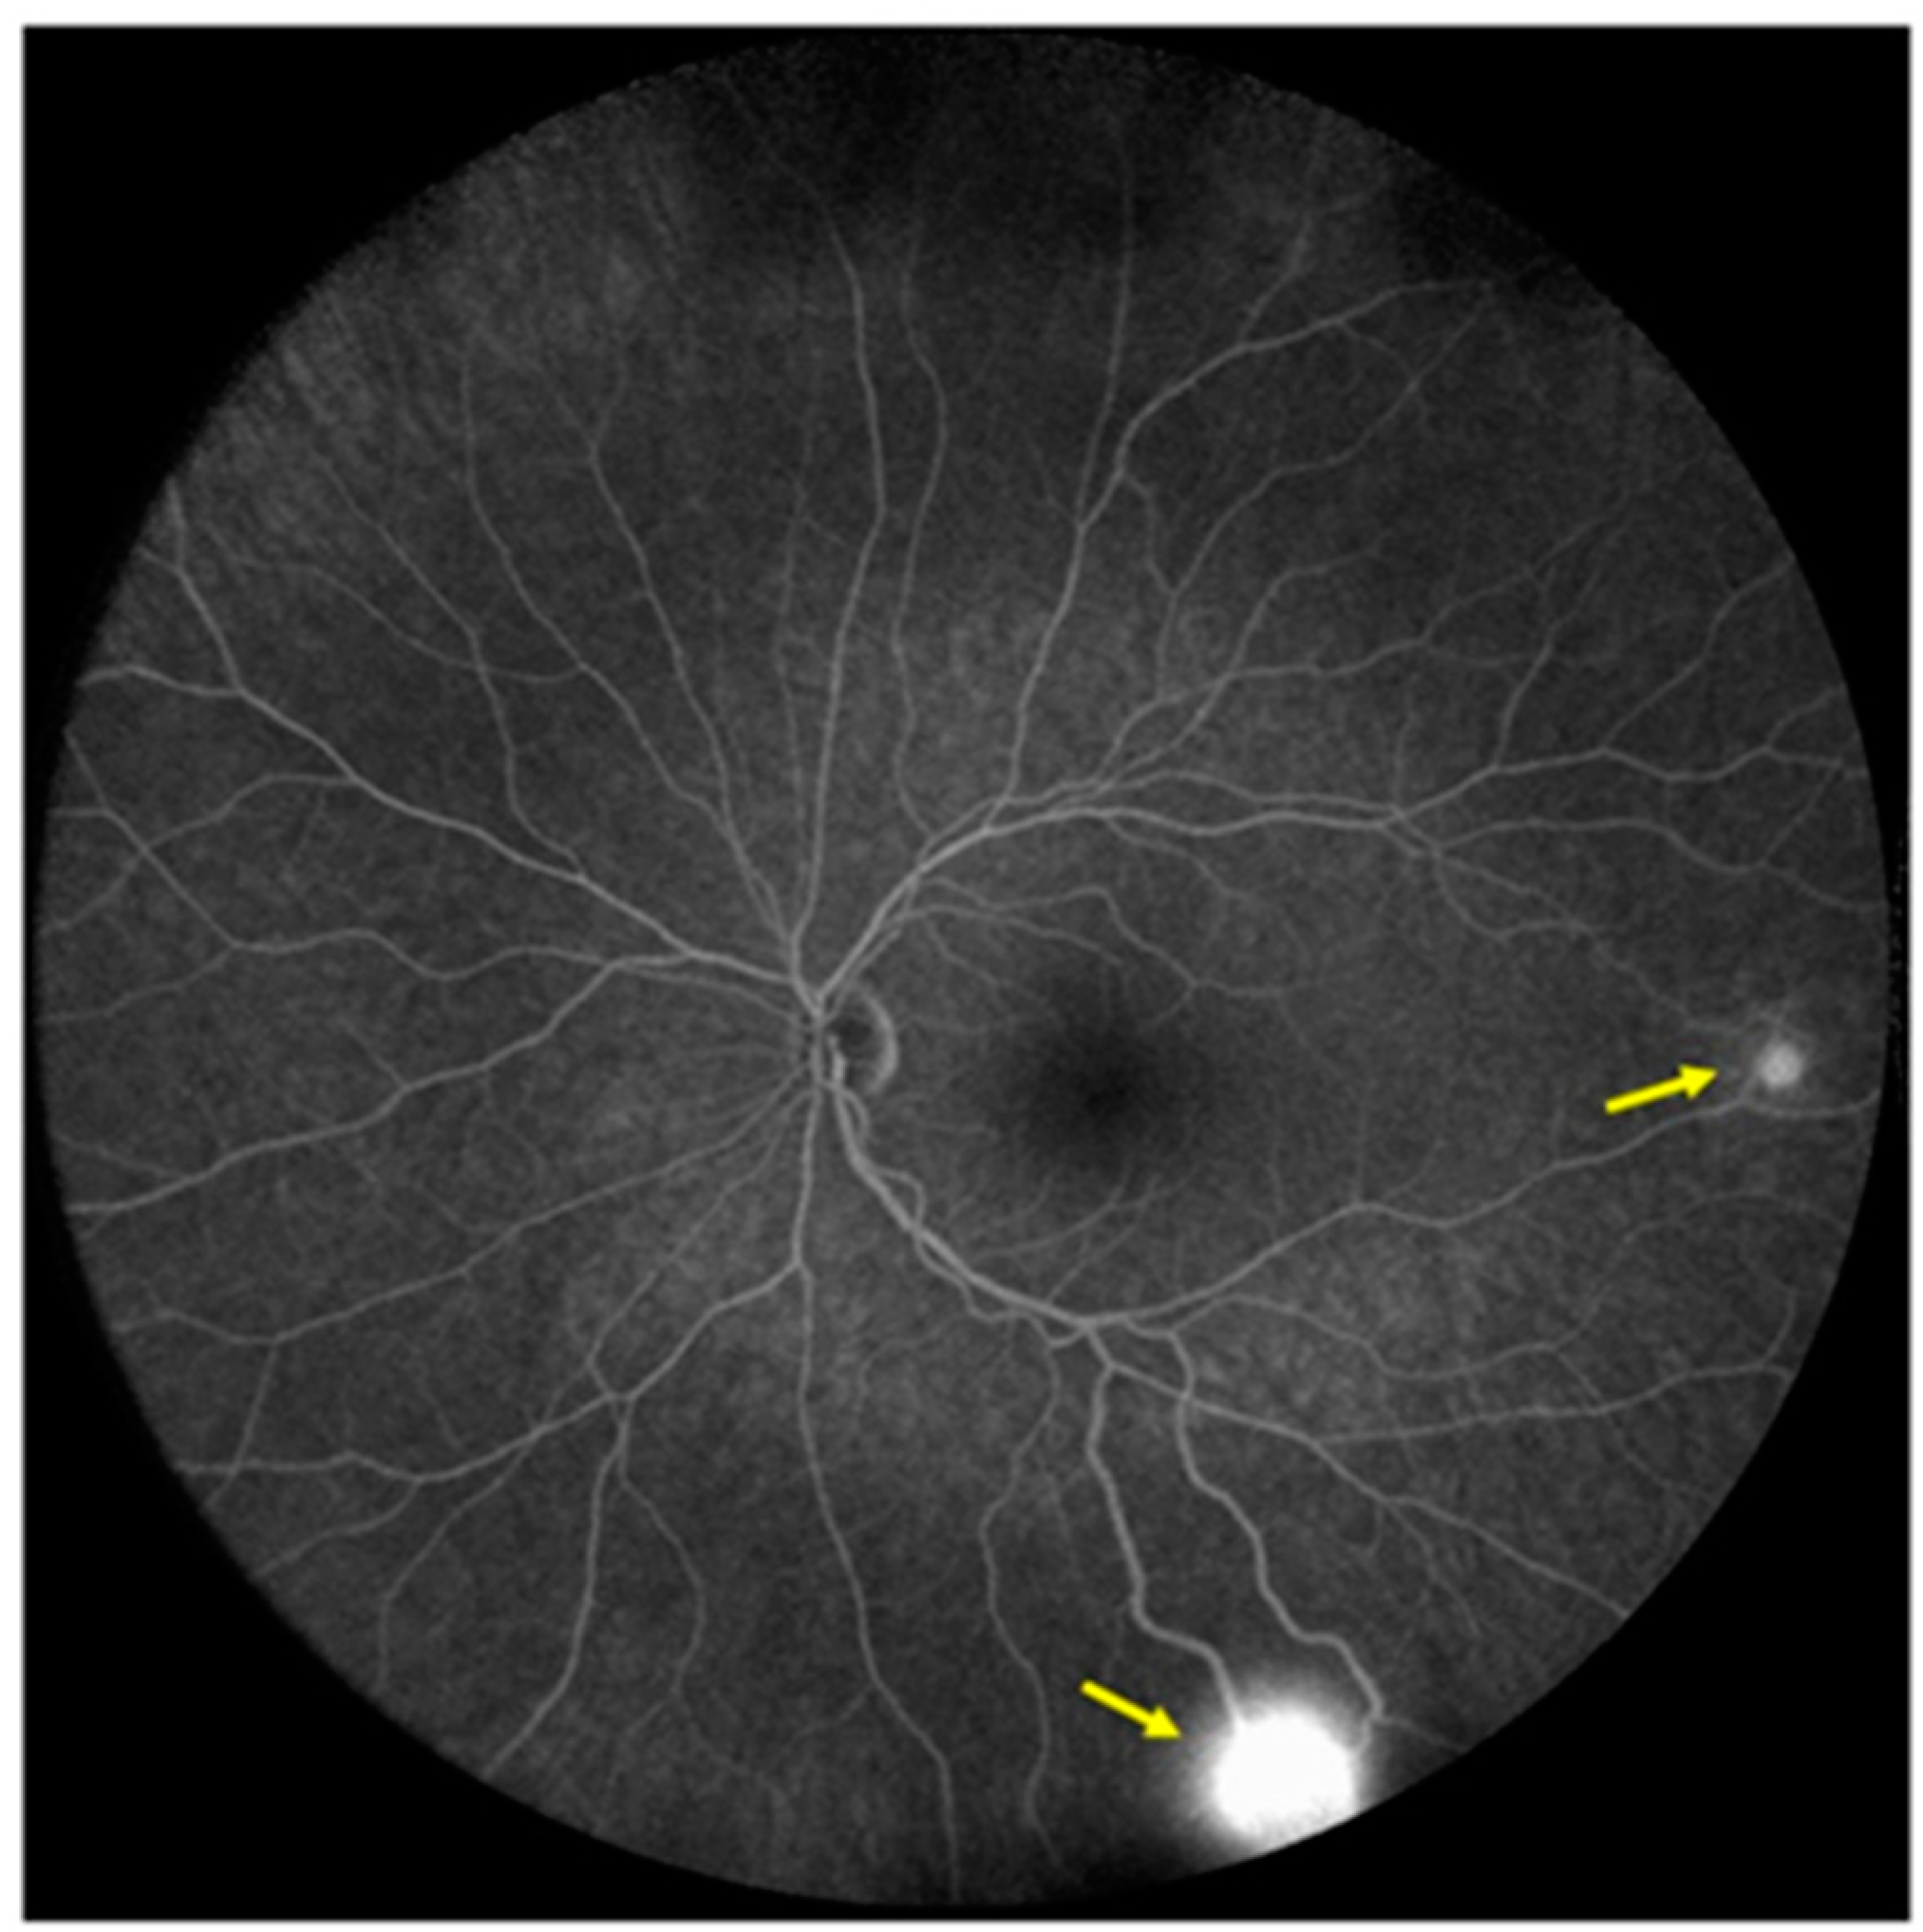

Two small peripheral retinal hemangioblastomas, some small telangiectatic changes, and a peripheral gliotic lesion with a vitreous traction were found on ophthalmological examination (Figure 5).

Figure 5.

Fluorescein angiography image of the patient’s left eye fundus; yellow arrows show retinal hemangioblastomas.

Patient first underwent a surgical procedure for the removal of a life-threatening expansive tumor near the 4th ventricle. Histological examination of the excised tumor confirmed the radiological diagnosis of hemangioblastoma (WHO grade I). Brainstem and cerebellar tumors, as well as a spinal cord tumor at the Th5 level, were removed in two additional surgical procedures in the following year. Retinal hemangioblastomas were successfully treated with laser photocoagulation. Since then, the patient has had regular check-ups. In the following three years there was no significant progression of the disease.